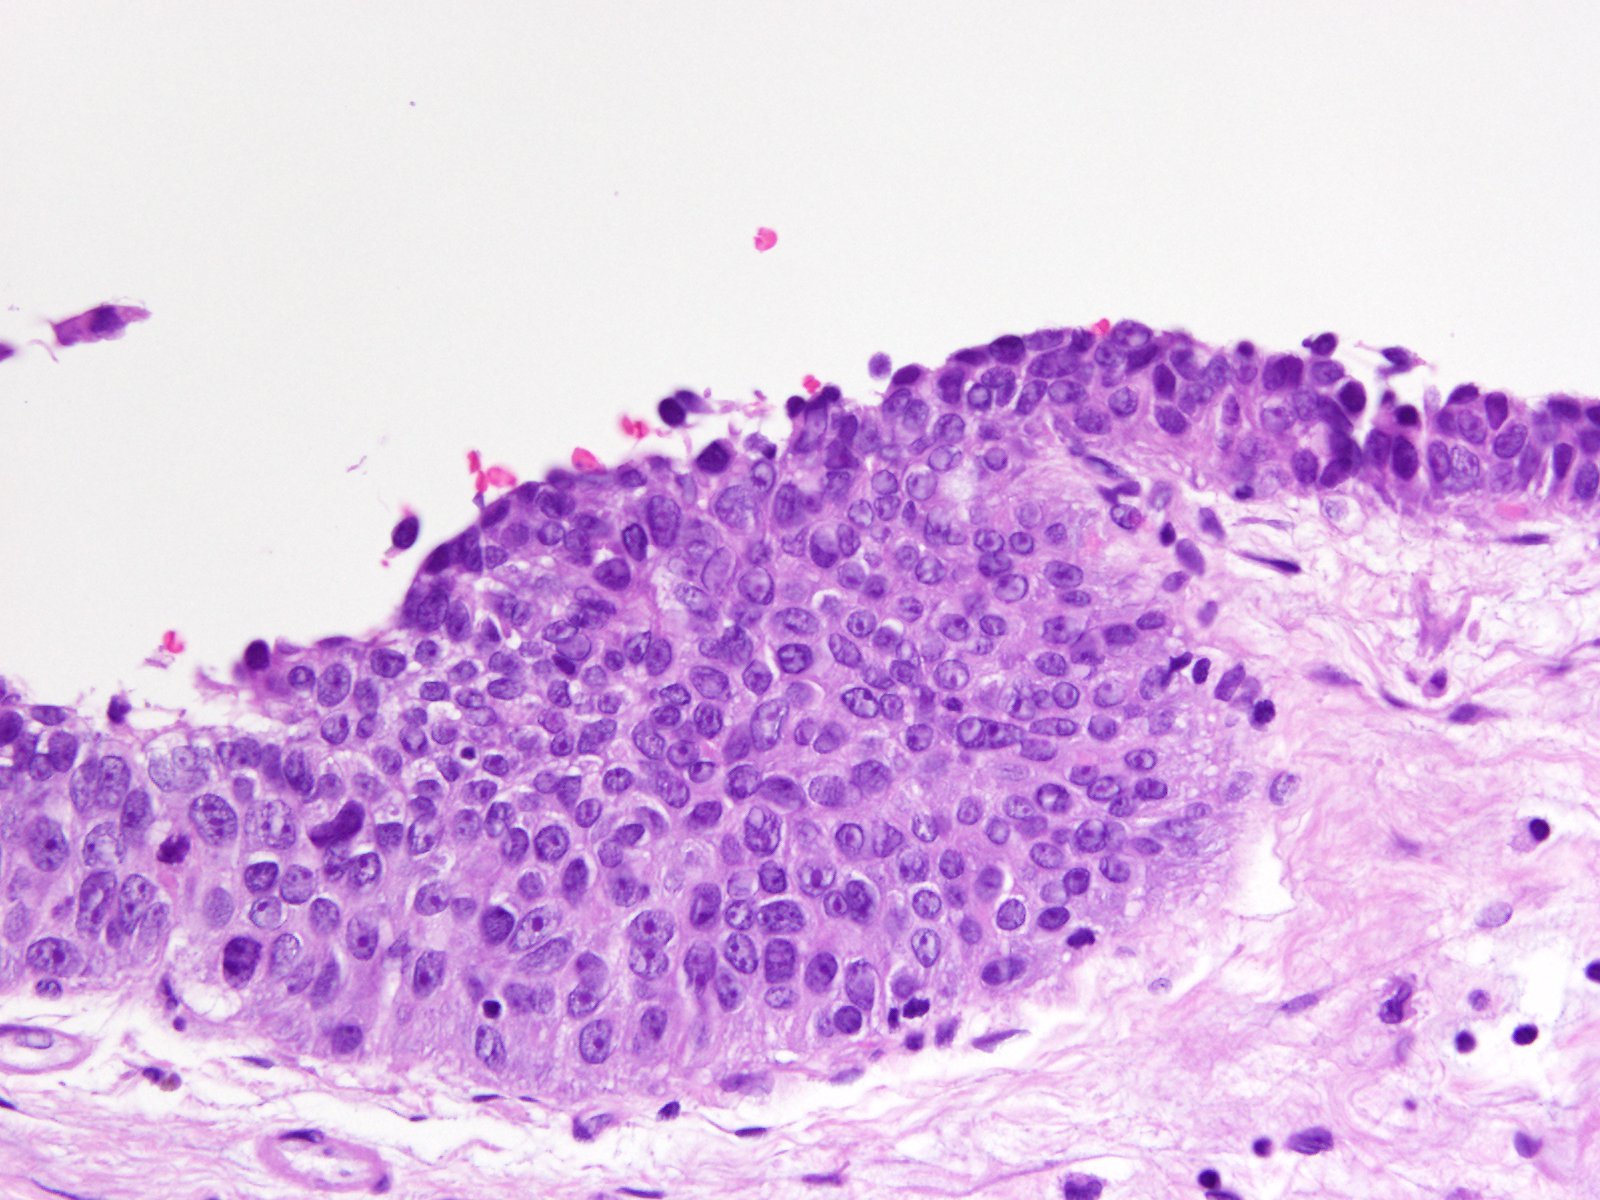

Bladder Flat Lesions

Case ID: 114

Reactive atypia

Atypia/dysplasia

Carcinoma in situ (CIS)